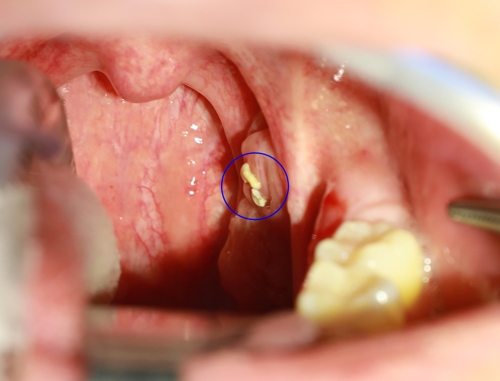

편도선염

편도선에 염증이 생기면 편도결석이 형성될 수 있고, 이는 심한 입냄새를 유발합니다. 편도결석은 편도선의 틈새에 음식물 찌꺼기와 세균이 결합해 생기는 작은 결석입니다. 편도선염이 반복된다면 수술적 제거를 고려해 볼 수 있습니다.